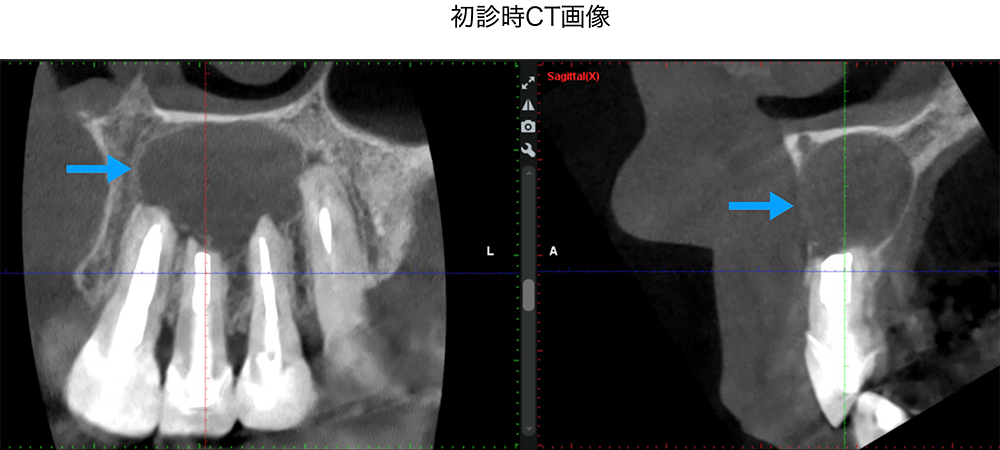

金山デンタルクリニックでは、治療の前に必ずCT撮影を行い、神経の本数や根の形、病変の大きさを正確に診査。治療の可能性や成功率まで含め、CTの画像を見せながら丁寧にご説明しています。治療後の経過もマイクロスコープやCT画像をお見せしながら、ご説明させていただきます。

金山デンタルクリニックでは、再治療が難しい症例や、根の先に大きな病変がある症例に対し、歯根端切除術などの外科的処置も行っています。